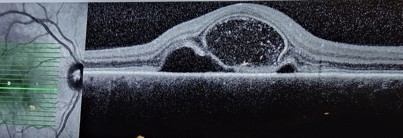

Her case concerned a 26-year-old who presented with sudden vision loss in one eye after a two-week history of mild upper respiratory infection. OCT showed a big central cyst within the bacillary layer of the retina (Fig 1). This is typical of acute posterior multifocal placoid pigment epitheliopathy (APMPPE), a form of cystic retinal oedema. Usually bilateral, it mostly appears in a person’s second to fourth decade, often after a virus and, importantly, may be associated with cerebral vasculitis.

A bacillary layer detachment (a term coined as recently as 2018) is separation of the bacillary layer of the retina due to a relative weakness in the myeloid layer. There is a breakdown of the retinal pigment epithelium blood retina barrier while the external limiting membrane is preserved, allowing fluid to get into the intra-retinal space. The fluid can often look quite turbid.

Fig 1. Bacillary layer detachment. A retinal cyst usually resolves in 4–8 weeks, but steroids may hasten the process